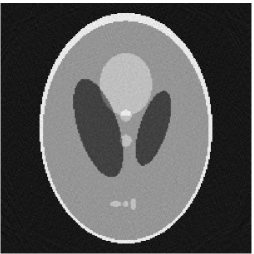

Furthermore, we used the classic ART iteration as the iteration operator in our numerical experiments. In order to compare the proposed superiorization algorithm with the classic superiorization algorithm, we applied the classic superiorization and -PP superiorization algorithm to two phantoms (see figure 1). The first one is the Shepp-Logan phantom[30], and the second one is the head phantom with a ghost which is invisible at 22 specified projection directions [10, 31]. In addition, we compare the performances of the two algorithms for the noiseless and noised data with different projections. In all experiments, the noised projection data was corrupted by additive Gaussian white noise with variance . We record the iterations, running time of program and mean square error (MSE) of different algorithms, where MSE is computed by

Noiseless projection data: Since the ghost in this phantom is invisible at 22 directions [10, 11], the reconstruction images usually suffer from artifacts. in our simulations, the projection data were collected in 112 and 82 directions: 90 and 60 with equal angle increments from to and 22 specified views in which the ghost is invisible [10]. Iteration procedures were terminated when for the noiseless projections.

The reconstruction images from the noiseless projection data were shown in the Fig. 6. For comparison, Table 3 present the iterations, MSE, Res and running time(RT) of different reconstruction results.